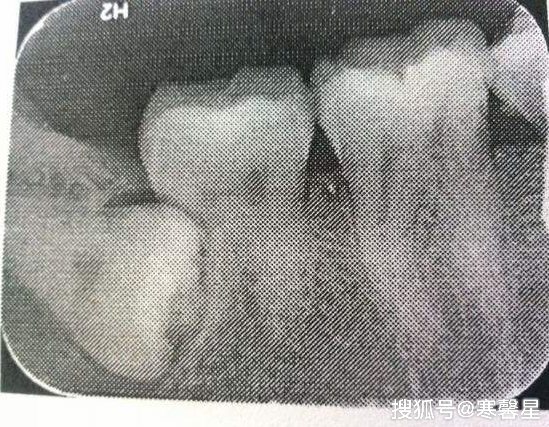

智齿非拔手术过程图解

1080x817 - 65KB - JPEG